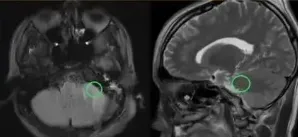

最终,手术如期进行。巴教授顺利为沫沫全切肿瘤,术后的沫沫并无新发神经损伤,运动功能也未受影响,而这一切,都得益于这位少年超乎寻常的毅力与决心。沫沫如愿为自己的未来扫除了一个障碍,我们更希望他能一直保持这份勇敢,坚毅前行!